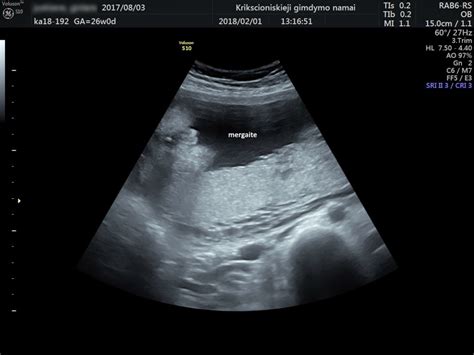

Sprando vaiskumo matavimas atliekamas ultragarsu 11-13 nėštumo savaitę (11+0 - 13+6). Tyrimo metu nustatomas vaisiaus amžius, įsitikinama, ar auga vienas vaisius, ar dvynukai, įvertinama gimdos ir placentos kraujo apytaka, gimdos kaklelio ilgis, apžiūrima, ar nematyti anomalijų (apsigimimų), ir matuojamas sprando vaiskumas.

11+0 - 13+6 nėštumo savaitę ultragarsinio tyrimo metu (kartais tiriama vaginaliniu davikliu) nustatomas vaisiaus amžius, įsitikinama ar auga vienas vaisius ar dvynukai, įvertinama gimdos ir placentos kraujo apytaka, gimdos kaklelio ilgis, apžiūrima ar nematyti anomalijų (apsigimimų) ir matuojama sprando vaiskuma (NT, angl. nuchal translucency), anksčiau vadinta „sprando raukšle“. Sprando vaiskumo matmuo ir nosies kaulo buvimas ar nebuvimas leidžia įtarti arba atmesti chromosomines vaisiaus ligas, dažniausiai 21 chromosomos trisomiją, t. y. Dauno sindromą. Jam būdinga stora vaisiaus sprando raukšlė: kuo ji storesnė, tuo Dauno sindromo tikimybė yra didesnė. Tyrimo rezultatas bus aiškus iš karto. Svarbu, kad embriono sprando vaiskuma nebūtų didesnė nei 3 mm.

Kuo didesnis sprando vaiskumo matmuo, tuo didesnė chromosomų anomalijų rizika (apsigimimų). Atminkite, kad šio matavimo tikslumas nėra šimtaprocentinis - priklauso nuo gydytojo patirties, vaisiaus pozicijos ir kt. Šio metodo patikimumas 80 proc. Ir atvirkščiai, jei sprando vaiskumo tyrimas nerodė rizikos, tai nereiškia, kad vaikutis tikrai gims sveikas.